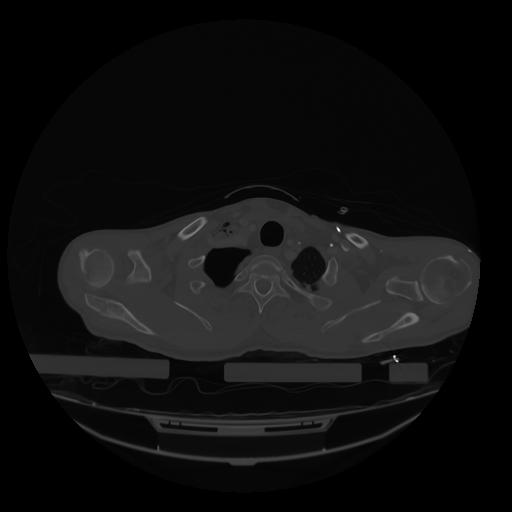

28 CUERPO,CE,Vol,2.0,CUERPO,,